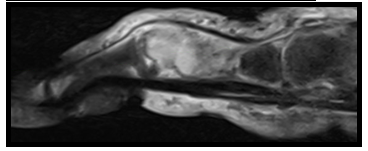

Unklarer osteolytischer Tumor am Ringfingergrundglied

Histologie vom Biopsat: Fibroblastenreiches spindelzelliges Stroma mit mehrkernigen Riesenzellen

Ergebnisse: Brauner Tumor – Osteitis fibrosa cystica.

Die Osteitis fibrosa cystica, auch brauner Tumor genannt, entsteht im Knochen aufgrund eines primären oder sekundären Hyperparathyreoidismus. Eine pathologisch erhöhte Parathormonsekretion stimuliert die Osteoklastenaktivität und führt zur Bildung von Hohlräumen im Knochen. Es kommt zu Einblutungen (Hämosiderinablagerungen → braun → brauner Tumor), die den osteoklastären Knochenabbau weiter fördern, so dass sich schließlich größere auch radiologisch nachweisbare Osteolysen bilden.

Histopathologisch zeigen sich zahlreiche Riesenzellen vom osteoklastischen Typ, so dass ein Riesenzellgranulom oder auch die aneurysmatische Knochenzyste in der Differentialdiagnose in Frage kommt.

Abbildung 2 [Fig. 2]